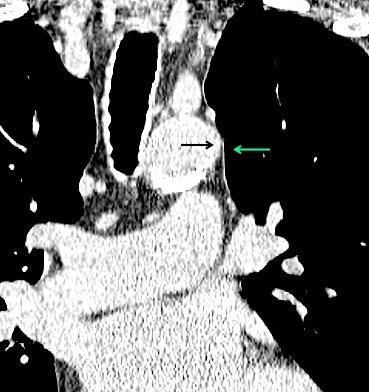

Edad: 40-50 años

3% segregan catecolaminas.

(En el área Paravertebral +/-50%.)

Intenso realce con el contraste.

32 años .Preeclampsia a los 19. Hipertensión no controlada. Masa paravertebral sólida que se realza intensamente con afectación ósea.

Yue Y t al. Asymptomatic left posterior mediastinal functional Paraganglioma. A case report. Medicine . 2019